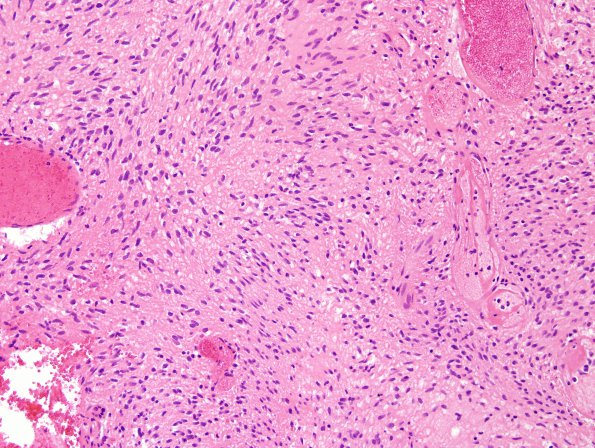

7B1-5 The tumor is composed of a cellular proliferation of cells with spindled morphology and round, ovoid, and spindle-shaped nuclei. Most of the cells have elongated, eosinophilic processes with indistinct cell borders. The nuclei are rather bland-appearing, predominantly ovoid in shape with mild contour irregularities and smooth, finely granular to vesicular chromatin; scattered atypical forms are identified. Vessels also show perivascular chronic inflammatory infiltrate, hemosiderin-laden macrophages and extracellular hemosiderin deposition resembling Schwannoma.